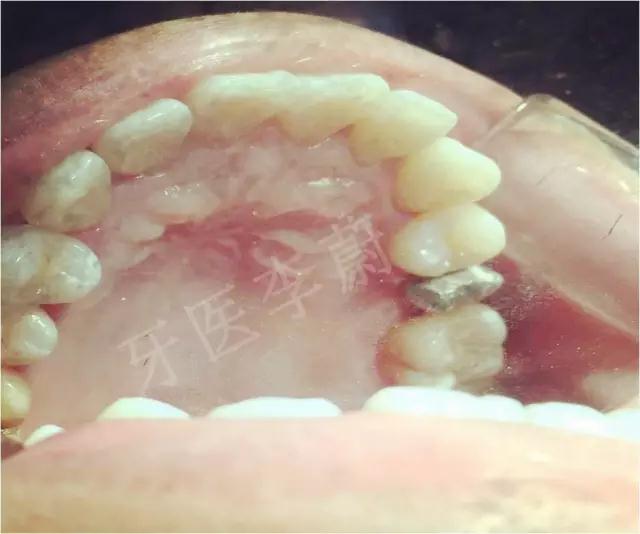

口腔检查:15冠部龋损,探及大量腐质,舌侧冠折至龈下约2mm,近、远中壁亦部分龋坏,松动Ⅰ°,叩痛(-) ,牙龈无瘘管,舌侧及近中被龈组织覆盖。

(2)切除增生牙龈组织,

(2)激光切除增生牙龈